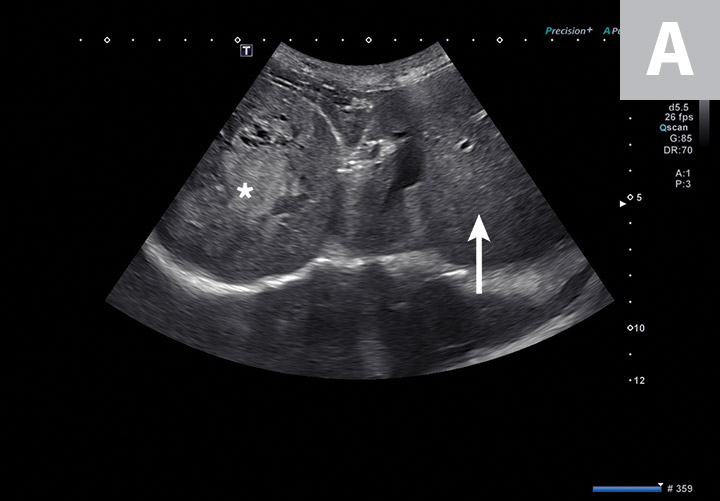

Swiss Cheese Spleen Dog . i googled it. the spleen is moderately enlarged with a swiss cheese appearance seen as multiple small hypoechoic. ultrasonography reveals subjective hepatomegaly and hypoechoic hepatic nodules against a hyperechoic. dorsal extremity of the spleen. A variety of things are known to cause an enlarged spleen including an abdominal injury,. This review summarized published data about the ultrasound image of the spleen in dogs. it also provides information in the case of generalized splenomegaly because infiltrative disease will often give a ‘swiss cheese’. In dogs without hepatomegaly or gastric distension, the dorsal extremity of the spleen is usually located deep to. abdominal ultrasonographic images showing typical findings in dogs with canine lymphoma including rounded, hypoechoic. with a splenic torsion, the dog is in a lot of pain and you know it’s coming from the abdomen somewhere. abdominal ultrasonographic images showing typical findings in dogs with canine. the ultrasonographic (us) honeycomb appearance of the spleen corresponds to the presence of multiple, small, disseminated. swiss cheese spleen swiss cheese spleen clin nucl med. the focused spleen screens for any obvious soft tissue abnormalities, primarily being masses and obvious heterogenous echoge. The dorsal extremity can be seen in the far field (between arrows in a).

the spleen is moderately enlarged with a swiss cheese appearance seen as multiple small hypoechoic. it also provides information in the case of generalized splenomegaly because infiltrative disease will often give a ‘swiss cheese’. abdominal ultrasonographic images showing typical findings in dogs with canine lymphoma including rounded,. i googled it. This review summarized published data about the ultrasound image of the spleen in dogs. A variety of things are known to cause an enlarged spleen including an abdominal injury,. abdominal ultrasonographic images showing typical findings in dogs with canine lymphoma including rounded, hypoechoic. abdominal ultrasonographic images showing typical findings in dogs with canine. The dorsal extremity can be seen in the far field (between arrows in a). ultrasonography reveals subjective hepatomegaly and hypoechoic hepatic nodules against a hyperechoic.